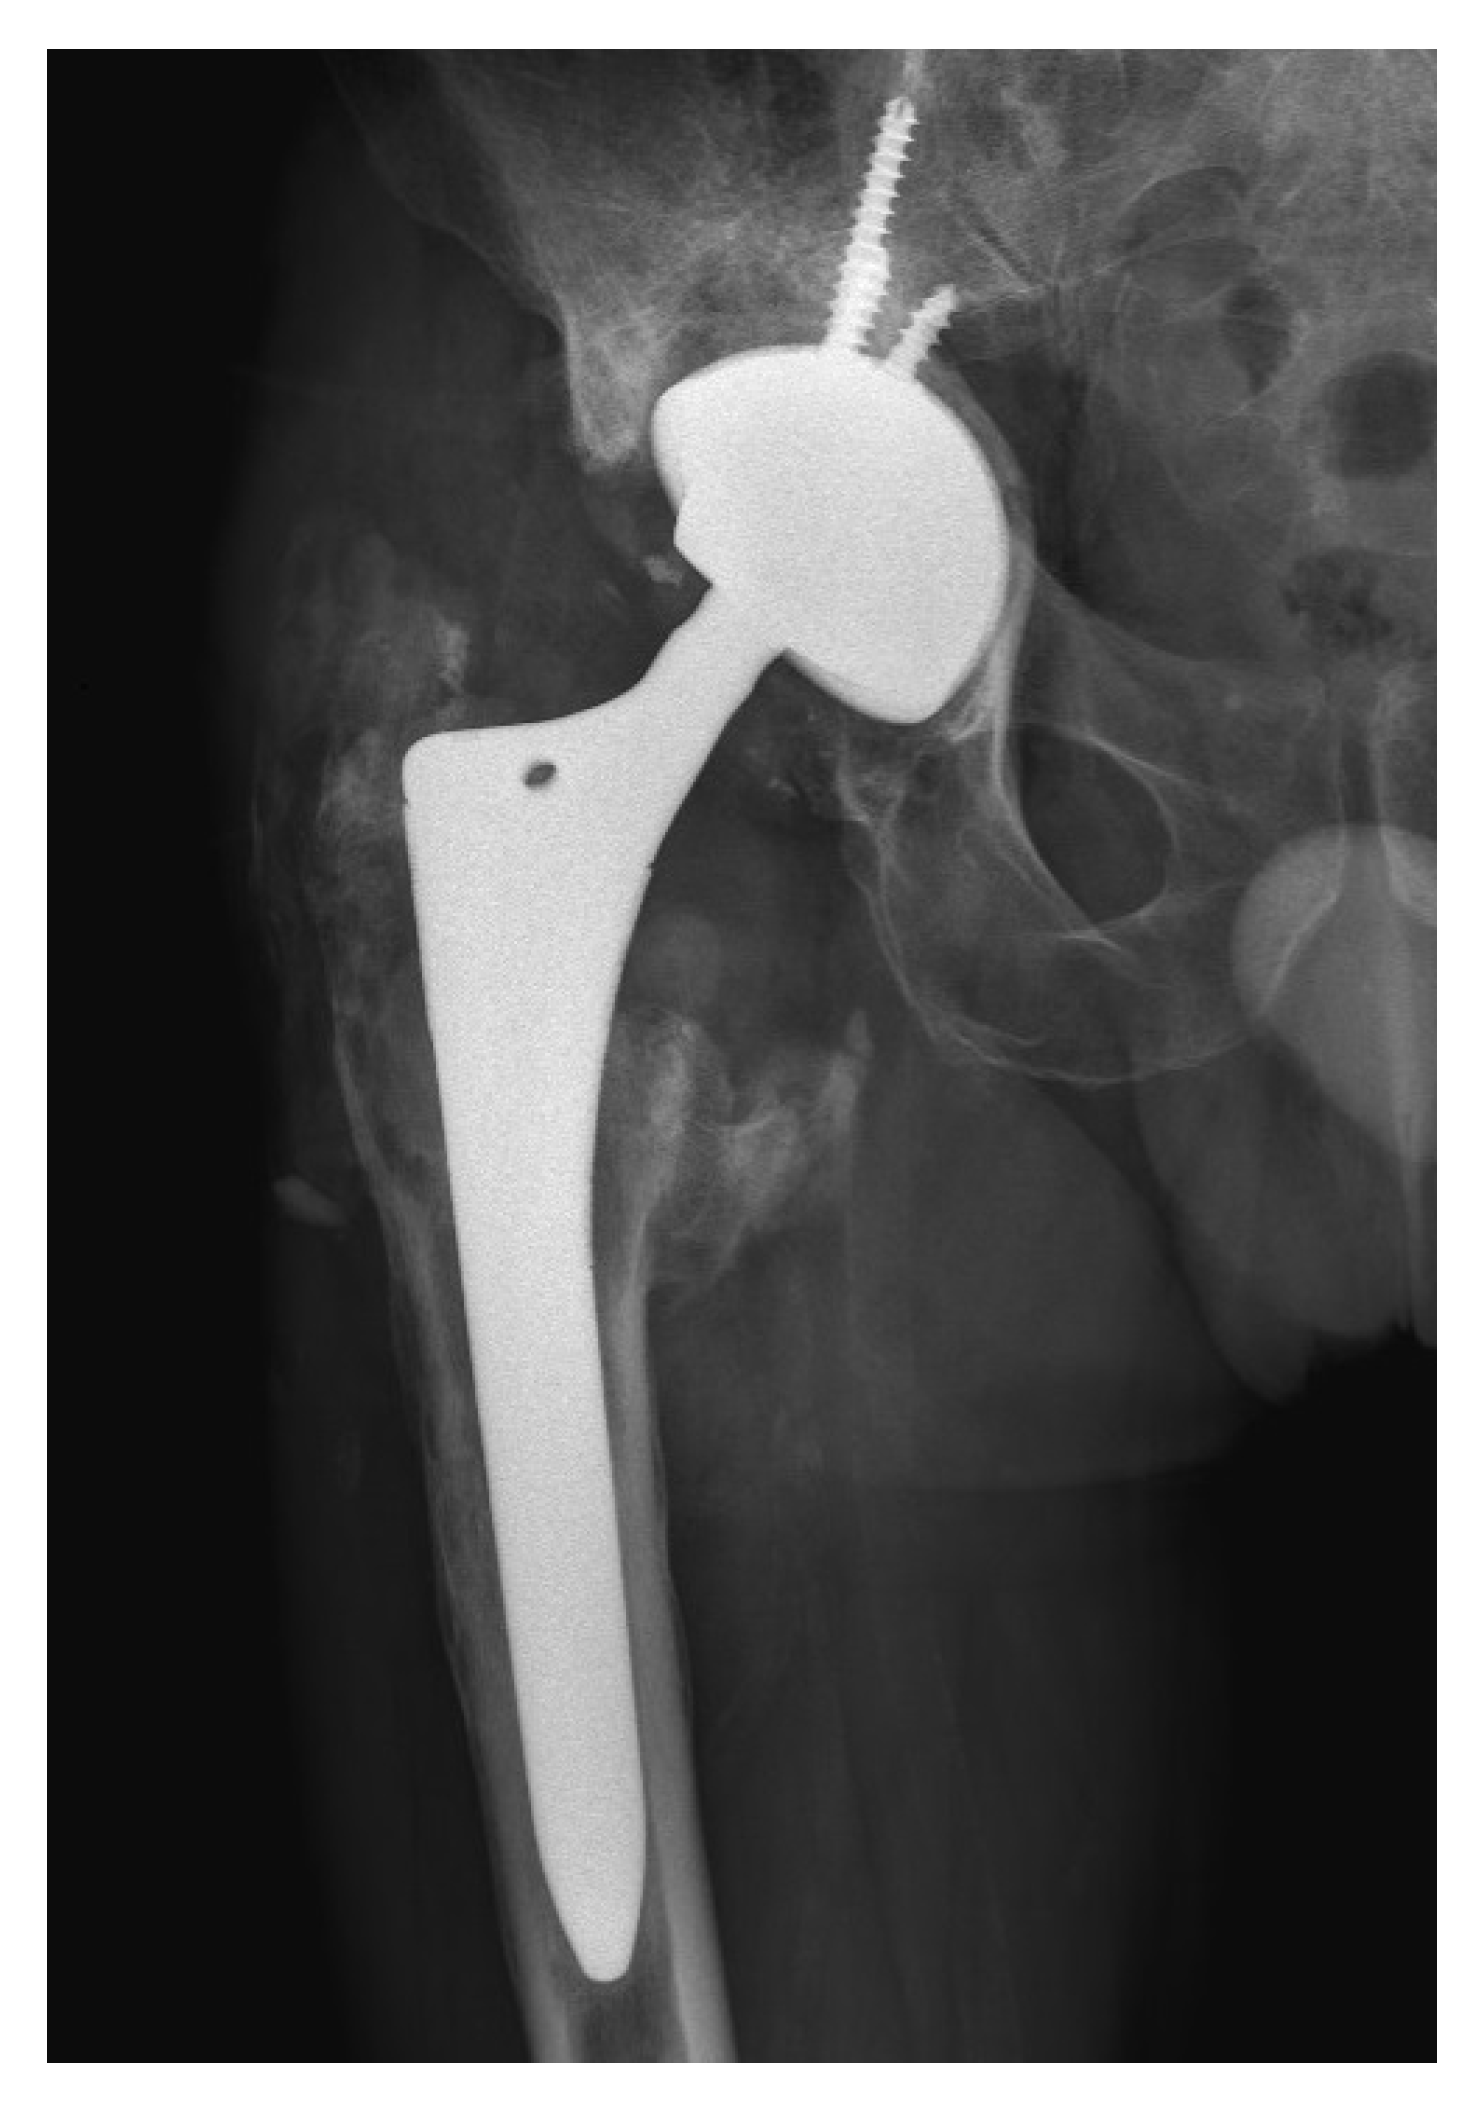

2. Case Presentation